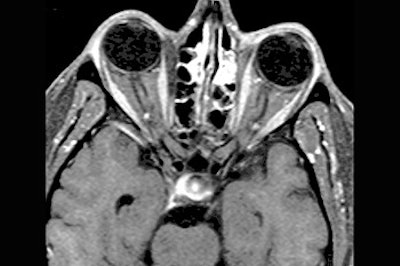

The patient underwent treatment with the antibiotic doxycycline for three weeks. Three months later, post-treatment MR exams showed complete resolution of the homogenous muscle thickening, and some inflammatory changes in the sinuses that eventually resolved themselves.

| Axial contrast-enhanced, fat-suppressed T1-weighted image through the orbits, post-treatment with doxycyline, demonstrates complete resolution of the previously noted homogeneous muscle thickening. There remain scattered inflammatory changes in the ethmoid sinuses and the left maxillary sinus. Images courtesy of Dr. Peter Som. |